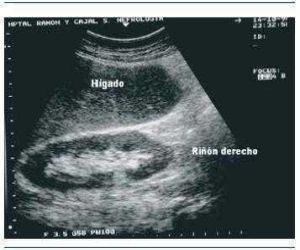

Ecografía renal

Es un examen seguro e indoloro en el cual se utilizan ondas sonoras para obtener imágenes de:

- Los riñones.

- Los uréteres.

- La vejiga.

Las imágenes en blanco y negro muestran la estructura interna de los riñones y los órganos relacionados.